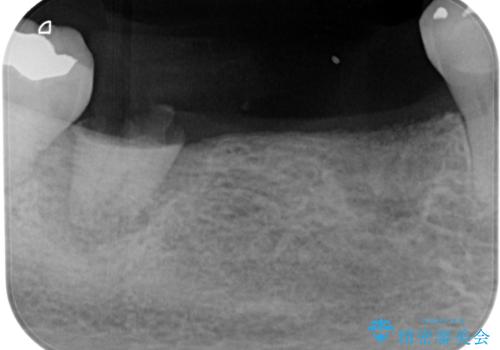

- 奥歯がなく、作ってもらった入れ歯もうまく使えないため、インプラント治療を希望して来院された患者様です。

入れ歯を装着すると咬み合わせの位置が大きく変化することが、入れ歯を使用できない理由でしたが、とにかく煩わしいのでインプラント治療を行いたいとのことでした。

インプラント埋入時に骨とインプラントの安定性を測定し、可能な限り早期に仮歯による咬合回復を図ることを前提に、インプラント補綴治療を行うこととしました。